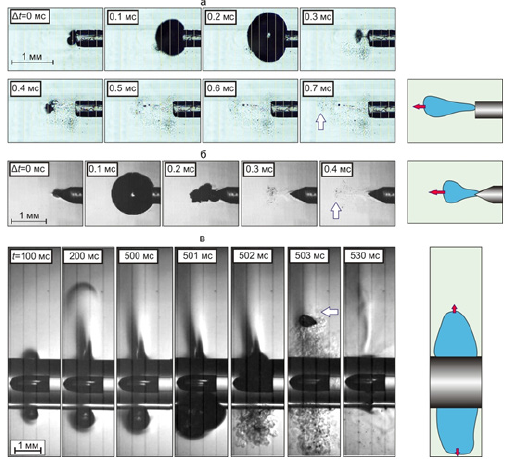

Figure 2A-2C shows the fragments of volumetric boiling water underheated to saturation temperature with the formation of heated water jets, propagating from the tips located in an open cuvette of laser optical fibers immersed in water. The figures show the direction of the jets and their corresponding heat flows, which propagate from the tips of optical fibers with different geometries. Figure 2A shows the heat flow from the optical fiber with a “radial” nozzle, Figure 2B- from the end-type optical fiber, Figure 2C- from the tip of the optical fiber sharpened like a cone.

It is clearly seen that from the fiber with a “radial nozzle” the heated jets propagate perpendicular to the axis of the fiber in the plane of the circle radially (Figure 2A), whereas from the fiber of the end type and the one sharpened like a cone, the jets move in the same direction - along the axis of the fiber forward from the end and the tip of the cone of the light guide (Figure 2B & Figure 2C). Accordingly, the heat flows concentrated in the jets also move in different directions perpendicular to the fiber with a “radial” nozzle and the fibers of the end and cone-sharpened type.

The process of jet formation during the boiling underheated to the saturation temperature is discussed in [6,7] and shown in Figure 3. Figure 3 illustrates the boiling process - the growth and collapse of one bubble under the action of laser heating of water in the vicinity of the tip of the end-type optical fiber (Figure 3A), the fiber sharpened like a cone (Figure 3B) and the fiber with a “radial” nozzle (Figure 3C).

As a result of the absorption of continuous laser radiation with a wavelength of 1.47 microns and a power of 7 watts in water near the tips of optical fibers, the water heats up and boils. The collapse of the bubble at the tip of the optical fibers leads to the generation of heated jets that transfer heat to the intima of the vein at high speed, leading to thermal modification (irreversible denaturation of proteins) of the venous wall.

Figure 3:“A” The growth and collapse of the vapor bubble during underheated bulk boiling of non-deaerated water under the action of continuous laser radiation with a wavelength of 1.47 μm with a power of 7 W, passing through the optical fiber with a diameter of 400 mm on quartz, the tip of which is shaped like the end of the cylinder (fiber socket type) (a) like a cone (b) and on the “radial» head of the fiber (c). “B”. Shooting speed 250,000 fps. Frame duration 1/100000 s. The optical fibers are arranged horizontally in the cuvette.